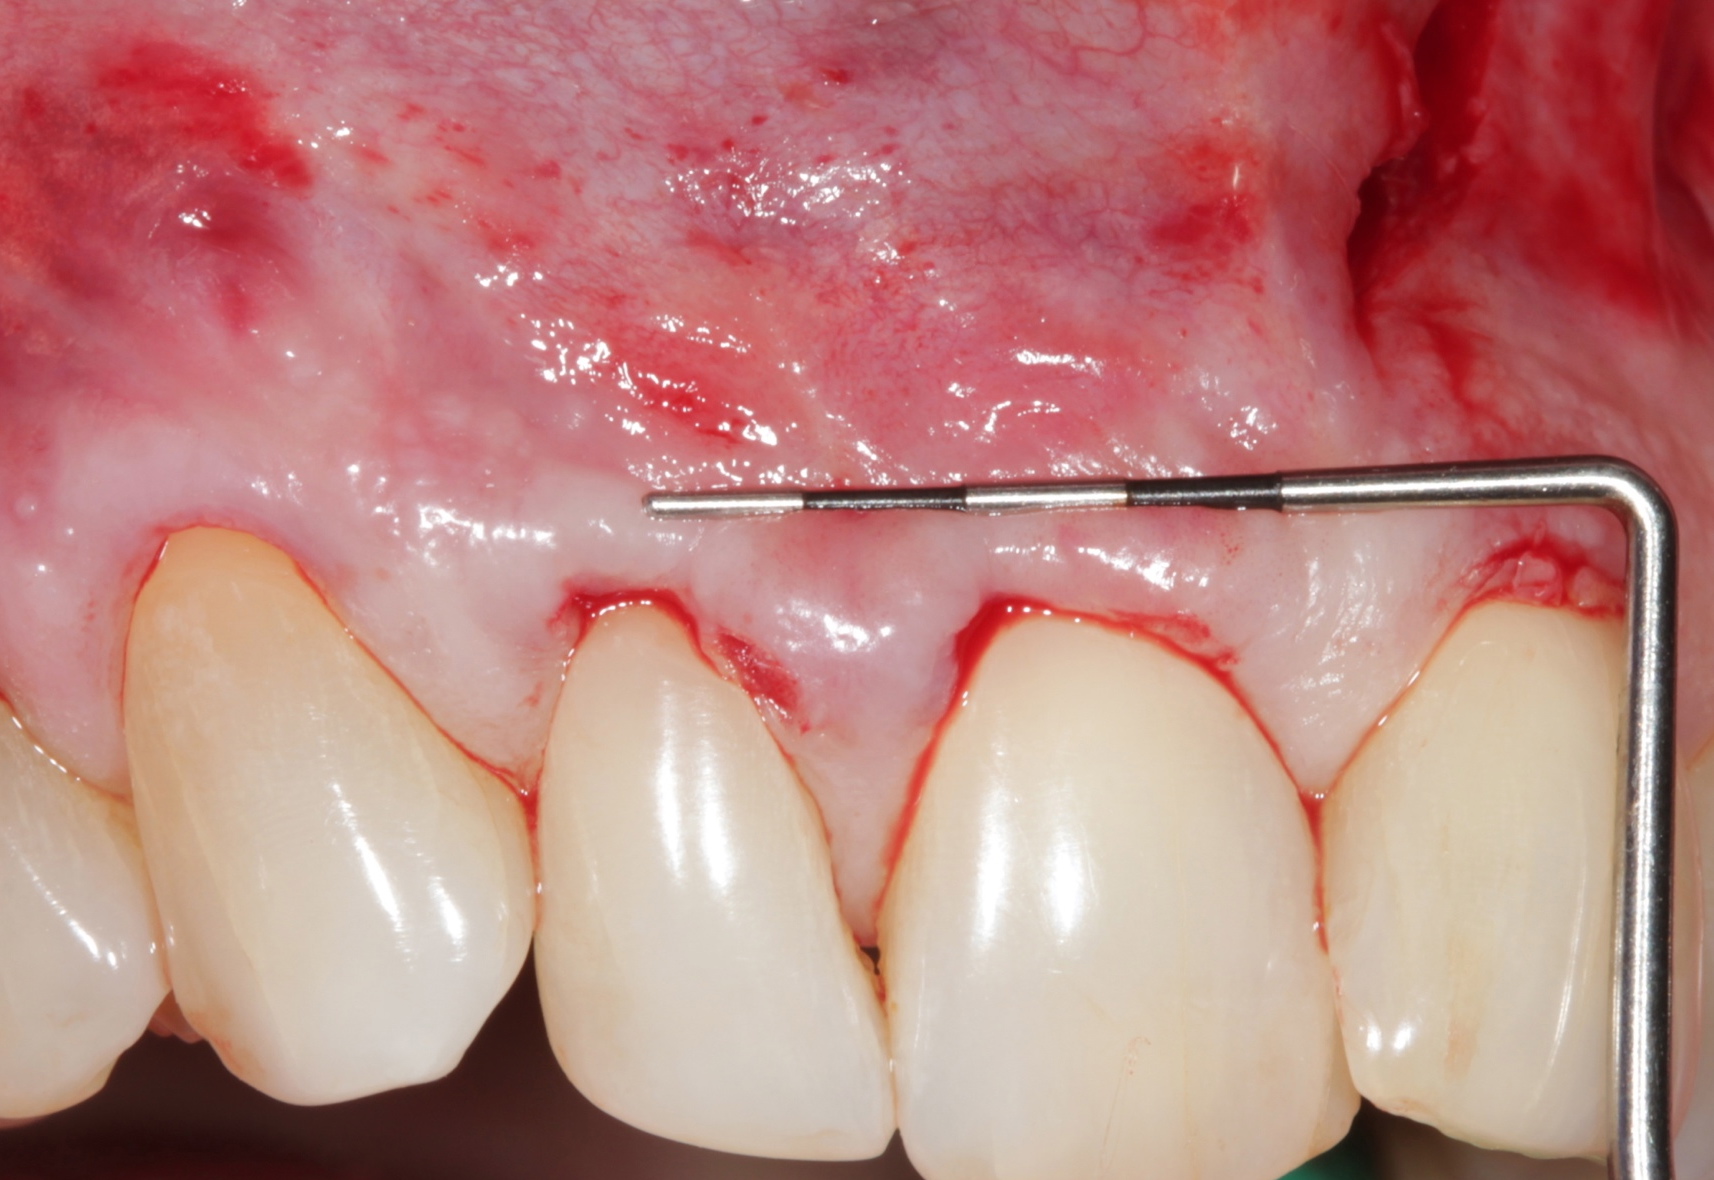

Fig 6. Incision and flap relaxation. A vestibular incision subperiosteal technique-access incision (horizontal mucosal incision) allows for a full-thickness horizontal dissection. A total flap relaxation enables the clinician to avoid uncontrolled flap pressure on the APRF membranes and allows complete and passive coronal positioning of the soft tissues.

Figure 6

Fig 7. APRF membrane placement. A “distal-mesial backpack” technique ensures a dense and complete packing of the APRF membranes in the pouch created. Three to 4 membranes are recommended per pair of teeth treated.

Figure 7